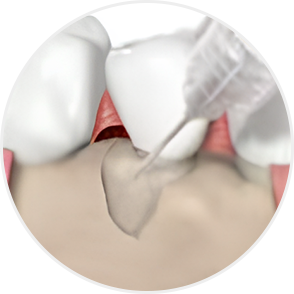

STEP 04

엠도게인 도포

잇몸재생술에 사용되는 엠도게인(Emdogain)은

단순한 약이나 충전재가 아닙니다.

치아가 처음 만들어질 때 쓰이는 단백질 성분을 본떠 만든 특수한 젤입니다.

엠도게인은 치아와 잇몸이 처음 자라던 환경을 다시 만들어주는 역할을 합니다.

그 결과 손상된 잇몸뼈나 치주조직이 스스로 회복할 수 있도록 도와줍니다.